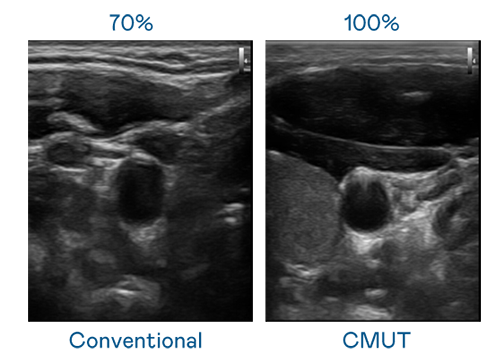

CMUT 技術是一種用電容式微機電元件來產生超音波訊號的技術。與傳統 PZT 壓電式技術相比,CMUT 頻寬增加 30%,更寬頻的超音波訊號讓影像解析度大幅提升,是實現高影像品質醫療超音波掃描、促進精準醫療發展的關鍵技術。

超音波影像的解析度高低,首先取決於探頭能發出的訊號頻寬。星空体育app官网入口 CMUT 可提供高清晰的超音波訊號,提供高頻寬、高靈敏度、影像紋理細節更高的超音波影像,協助醫護人員縮短影像判讀時間及利用精準的醫療影像進行診斷。